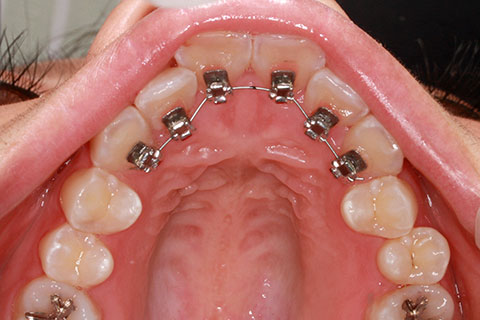

治療中(開始直後)

治療中(開始半年後)